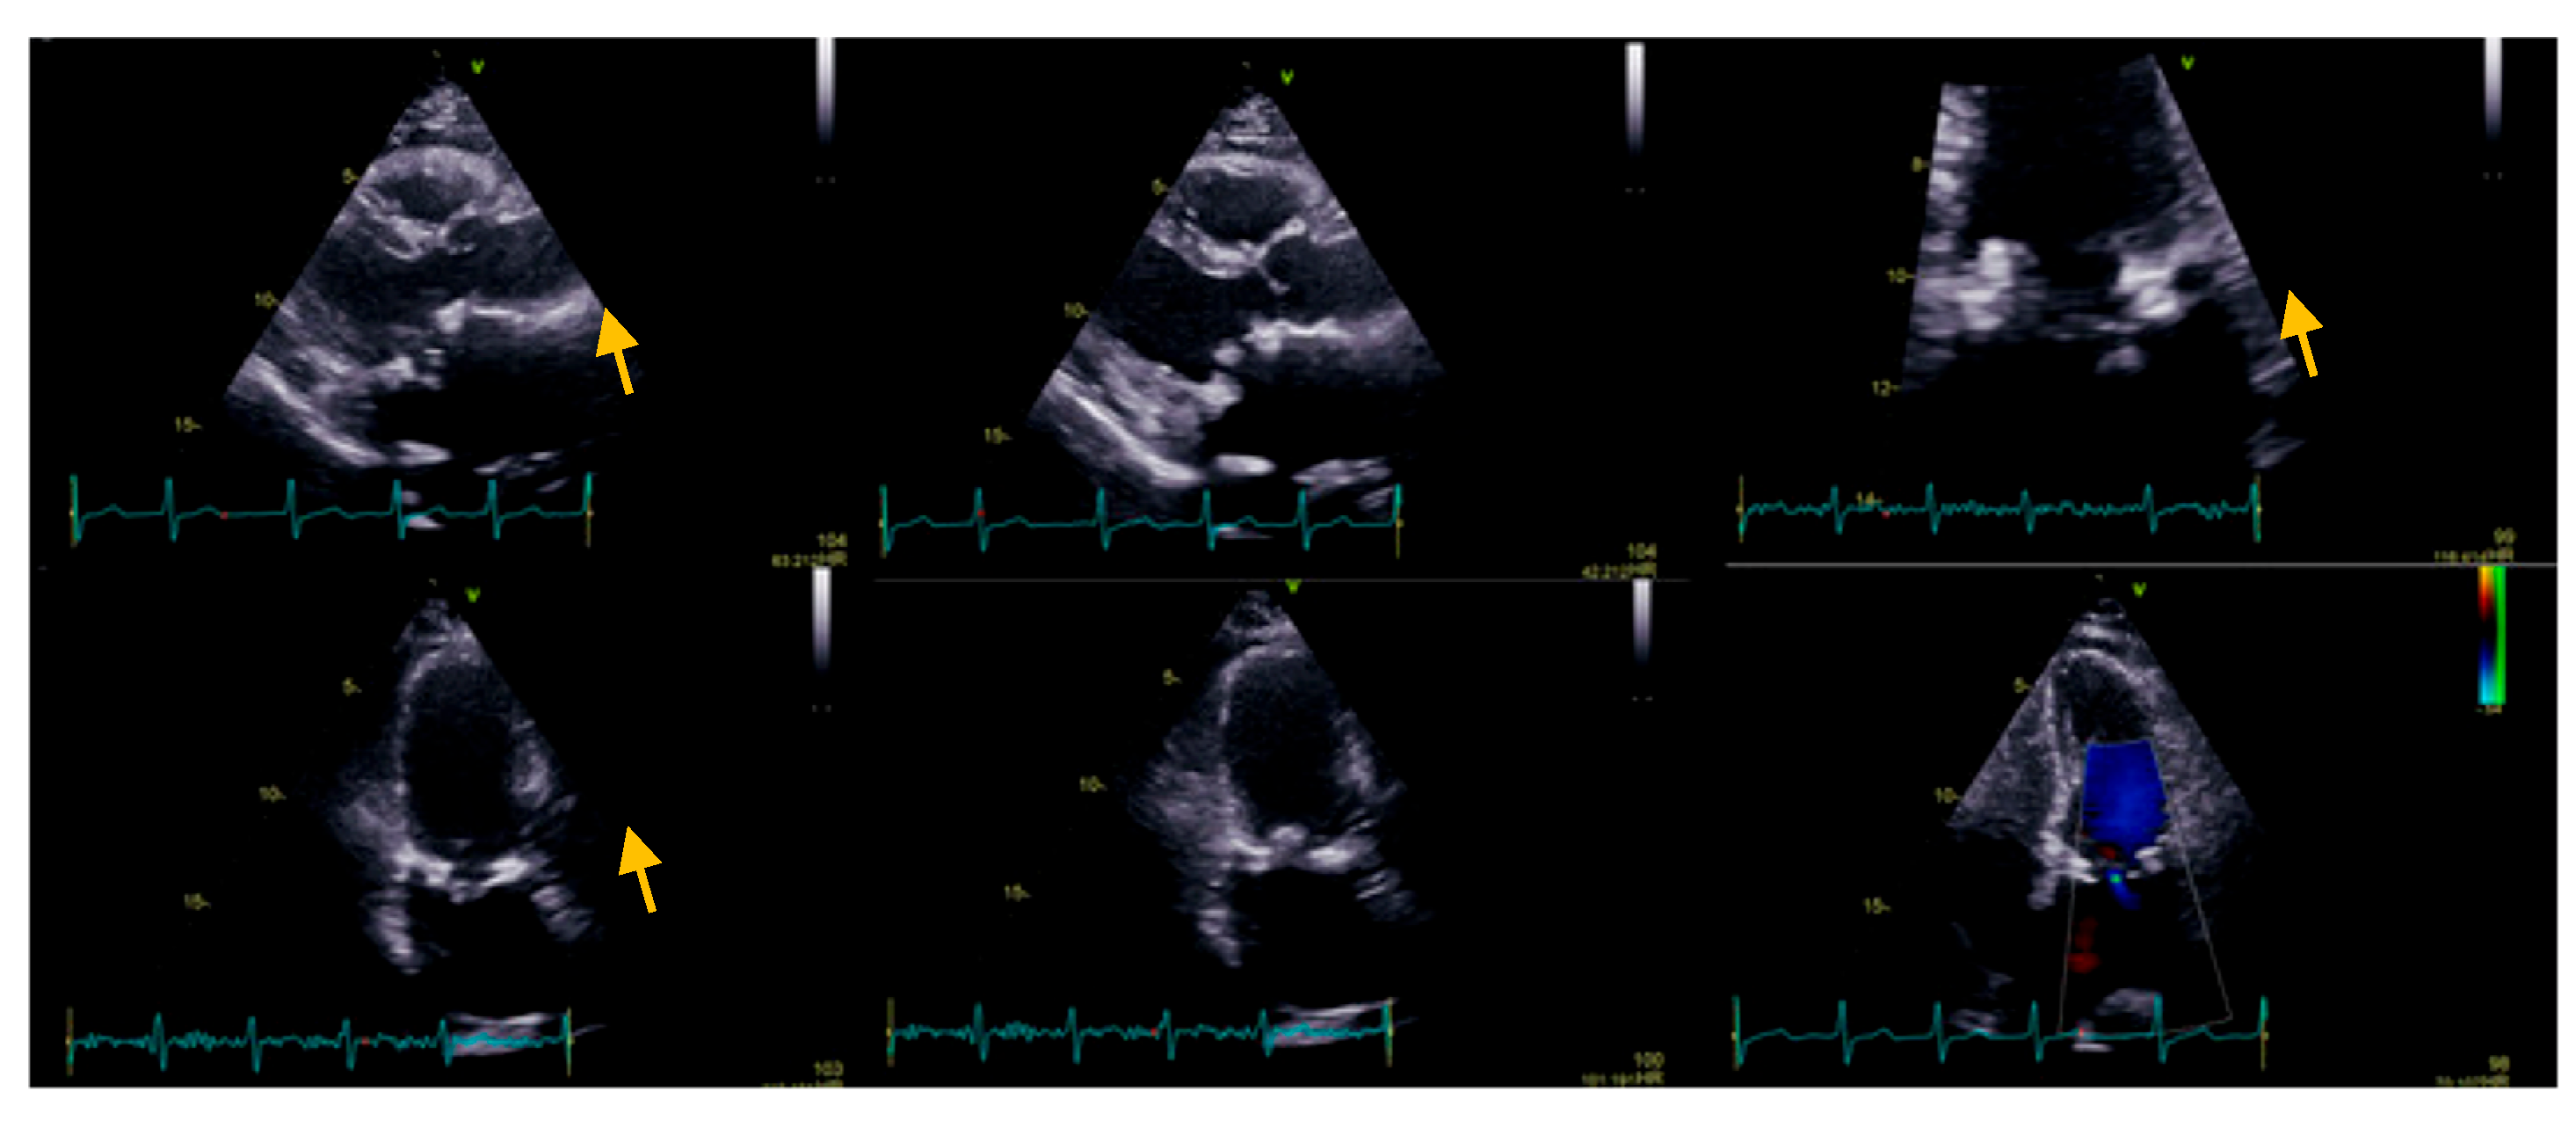

:1. Case Presentation